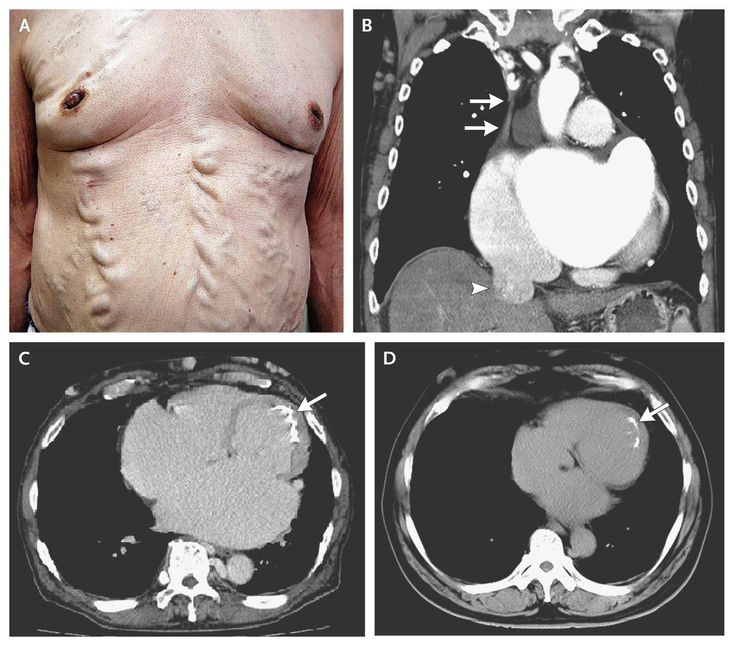

A 68-year-old man who had Behçet's disease with a 30-year history of oral and genital ulcers and erythema nodosum presented with progressive leg edema and dyspnea. The physical examination revealed varices of the chest and abdominal wall (Panel A), caused by collateral circulation associated with obstruction of the superior vena cava (SVC). Chest computed tomography (CT) showed SVC obstruction (Panel B, arrows) and dilatation of the inferior vena cava (arrowhead). Endocardial calcification on the midlateral and apical wall (Panel C, arrow) was more extensive than that seen on imaging performed 11 years earlier (Panel D, arrow), and there was increased dilatation of the right ventricle and both atria. A restrictive cardiomyopathy with endomyocardial fibrosis, which can be a complication of Behçet's disease, was diagnosed on the basis of echocardiography (video) and cardiac catheterization (including endomyocardial biopsy). After diuresis, the edema and dyspnea improved, but the varices of the trunk and lower limbs remained.